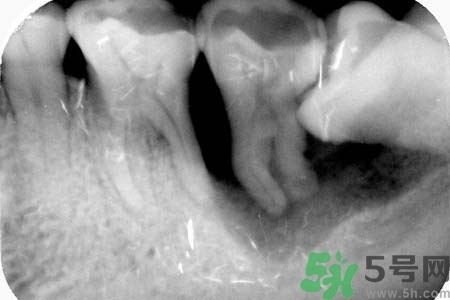

如果發(fā)現(xiàn)自己的智齒橫著長了,為了不讓智齒阻生引起其他的危害,我們一定要盡快把橫著長的智齒拔除,而且不需要鑲牙,拔掉之后有助于身體健康,還可以保護附近其他牙齒。但是,我們還要重視一點,拔智齒是一種牙科門診手術,要求醫(yī)生的技術水平要比較高,因為橫生的智齒,拔除的時候難度更大,首先要將黏膜切開,去骨之后才可以拔除的,這不是普通的牙醫(yī)可以把握好的。所以,小編在此提醒各位患者,務必選擇正規(guī)的牙科醫(yī)院,由專業(yè)的牙科醫(yī)生進行拔除手術。

智齒橫著長在拔除的時候需要遵循一些原則。正常情況下,生長情況沒有出現(xiàn)異常的智齒盡量要保留下來,不要隨便進行拔除。特別是那些生長了很多年的智齒。只有當智齒非正常生長,出現(xiàn)一些臨床癥狀的時候,才有拔除的需要。而且,在進行拔除手術之前,一定要先拍攝牙片,確定智齒生長異常再進行拔除。還有,發(fā)炎的智齒也必須要拔掉。但是如果炎癥消退,而且沒有出現(xiàn)復發(fā)的話,也可以不拔。

智齒橫著長具有很大的危害,它會擠壓附近的牙齒,嚴重時會導致整排的牙齒看起來都不整齊。而且還會影響到患者的咀嚼功能。智齒阻生跟前牙間會容易殘留食物殘渣,積累細菌,引發(fā)齲齒或冠周炎。如果一旦出現(xiàn)冠周炎就會反復地發(fā)作。智齒橫著長還會影響牙齒的咬合,長期下來更會引發(fā)下頜疼痛、夜磨牙等。很多20多歲左右的年輕人,總是覺得牙齒疼痛,去醫(yī)院檢查都會發(fā)現(xiàn)是因為智齒橫著長。但是智齒橫著長很難察覺,通常都是是引發(fā)了疼痛,患者才會開始所察覺。

智齒的生長,關鍵看你牙床的位置、頜骨的空間是否夠,如果夠,是根本不會疼的。智齒如果被阻生在頜骨里,或根本就不見萌出?;蚴菍е缕渌例X排列擁擠或移位,從而使局部牙齒出現(xiàn)齲齒、感染或牙齦疼痛。阻生的智齒在頜骨內的位置也是異常的,有時甚至呈水平阻生。這種情況最好是拔去。另外,你疼痛得不行了,也最好去醫(yī)院處理掉。其他情況最好就不要去拔,由于智齒在口腔最內側,最難操作,操作不當反而有害。用麻藥也不是什么好東西。在排除以上情況,你不想拔的話,給你幾點建議: